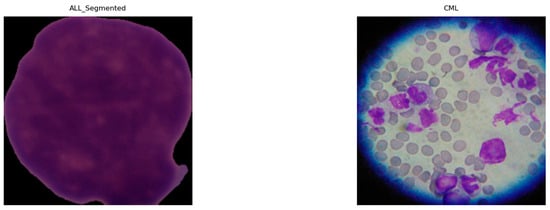

Demystifying Deep Learning Decisions in Leukemia Diagnostics Using Explainable AI

by Shahd H. Altalhi and Salha M. Alzahrani

Diagnostics 2026, 16(2), 212; https://doi.org/10.3390/diagnostics16020212 - 9 Jan 2026

Background/Objectives: Conventional workflows, peripheral blood smears, and bone marrow assessment supplemented by LDI-PCR, molecular cytogenetics, and array-CGH, are expert-driven in the face of biological and imaging variability. Methods: We propose an AI pipeline that integrates convolutional neural networks (CNNs) and transfer [...] Read more.

Background/Objectives: Conventional workflows, peripheral blood smears, and bone marrow assessment supplemented by LDI-PCR, molecular cytogenetics, and array-CGH, are expert-driven in the face of biological and imaging variability. Methods: We propose an AI pipeline that integrates convolutional neural networks (CNNs) and transfer learning-based models with two explainable AI (XAI) approaches, LIME and Grad-Cam, to deliver both high diagnostic accuracy and transparent rationale. Seven public sources were curated into a unified benchmark (66,550 images) covering ALL, AML, CLL, CML, and healthy controls; images were standardized, ROI-cropped, and split with stratification (80/10/10). We fine-tuned multiple backbones (DenseNet-121, MobileNetV2, VGG16, InceptionV3, ResNet50, Xception, and a custom CNN) and evaluated the accuracy and F1-score, benchmarking against the recent literature. Results: On the five-class task (ALL/AML/CLL/CML/Healthy), MobileNetV2 achieved 97.9% accuracy/F1, with DenseNet-121 reaching 97.66% F1. On ALL subtypes (Benign, Early, Pre, Pro) and across tasks, DenseNet121 and MobileNetV2 were the most reliable, achieving state-of-the-art accuracy with the strongest, nucleus-centric explanations. Conclusions: XAI analyses (LIME, Grad-CAM) consistently localized leukemic nuclei and other cell-intrinsic morphology, aligning saliency with clinical cues and model performance. Compared with baselines, our approach matched or exceeded accuracy while providing stronger, corroborated interpretability on a substantially larger and more diverse dataset. Full article

Show Figures

Figure 1